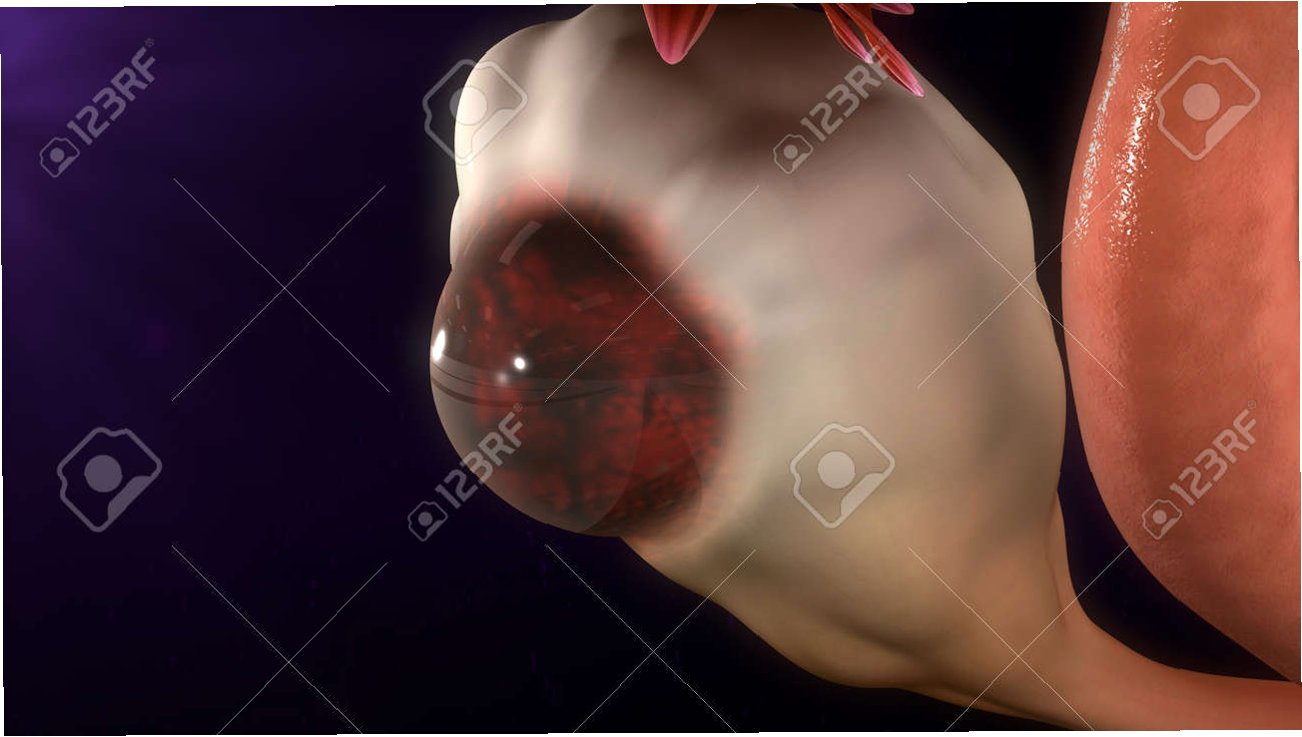

난소 낭종은 난소에 물이 찬 혹이 생기는 증상으로, 난소는 여성의 배란과 호르몬 생성을 담당하는 중요한 기관입니다. 일반적으로 두 가지 종류의 난소 낭종이 있으며, 기능성 낭종은 난포가 제대로 성숙하지 못해 생기는 것이고, 난포성 낭종은 배란 후에도 난포가 남아 있을 때 발생합니다. 대부분의 경우 크기가 크지 않으면 자각 증상이 없지만, 일부는 복부 팽만감이나 통증을 유발할 수 있습니다.

난소 낭종은 대개 자연적으로 사라지지만, 주의가 필요합니다. 만약 난소 낭종이 지속적으로 관찰된다면, 크기와 형태에 따라 수술 여부가 결정됩니다. 특히 가족력이 있거나 유방암, 난소암을 앓았던 경우에는 더욱 신중하게 접근해야 합니다. 폐경 여성의 경우, 난소 낭종의 악성 가능성이 높아지므로 수술이 권장됩니다.